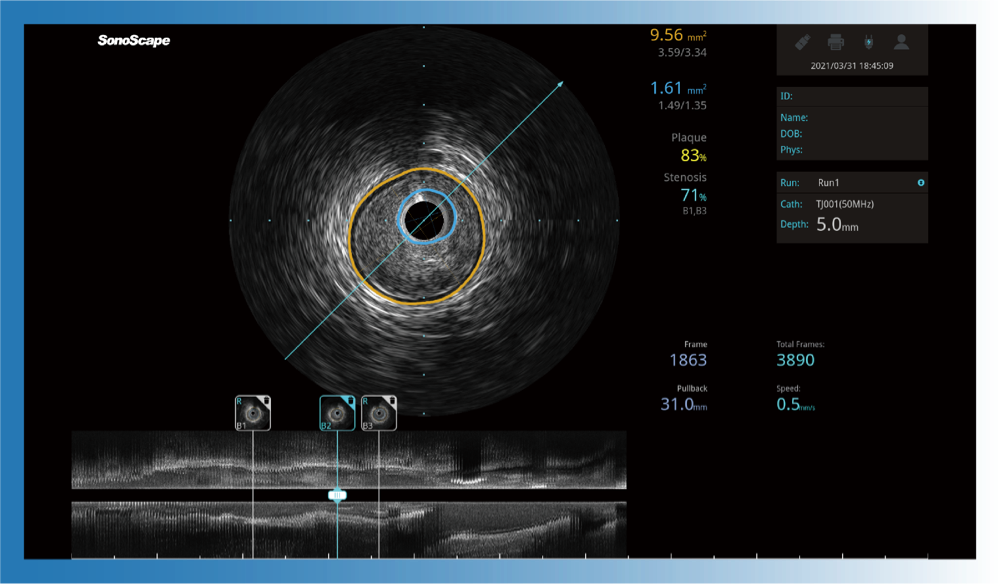

治疗前后两次测量录像对比

简化疗效评估

一键智能描迹,自动测量斑块负荷、面积狭窄率等指标,准确率高于90%